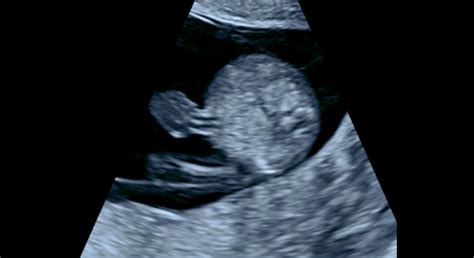

Počas tehotenstva je pravidelné sledovanie rastu a vývoja plodu nevyhnutné pre zabezpečenie jeho zdravia. Lekári využívajú na tento účel ultrazvukové vyšetrenia, známe aj ako fetálna biometria. Táto metóda umožňuje presné meranie rôznych anatomických vlastností plodu, ktoré slúžia ako ukazovatele jeho rastu a vývojového štádia.

- CRL (Crown-Rump Length): Temeno-kostrčová vzdialenosť. Toto je prvé meranie, ktoré sa vykonáva približne od šiesteho týždňa tehotenstva až do 20. týždňa. Meria sa od temena hlavy po kostrč a je kľúčové na presné určenie gestačného veku v raných fázach tehotenstva.

- BPD (Biparietal Diameter): Priečny priemer hlavičky. Meria sa od 14. týždňa tehotenstva a je jedným z najspoľahlivejších parametrov na určenie gestačného veku, najmä v období medzi 14. až 24. týždňom.

- HC (Head Circumference): Obvod hlavičky. Doplňujúci parameter k BPD, ktorý tiež slúži na určenie gestačného veku plodu.

- FL (Femur Length): Dĺžka stehennej kosti. Toto meranie je jedným z najpresnejších parametrov na určenie gestačného veku v období od 10. do 25. týždňa tehotenstva.

- AC (Abdominal Circumference): Obvod bruška. Tento parameter, hoci menej spoľahlivý pre určenie gestačného veku, je kľúčový pre odhad hmotnosti plodu.

- EFW (Estimated Fetal Weight): Odhadovaná hmotnosť plodu. Vypočítava sa na základe viacerých parametrov, najmä AC a FL, a je obzvlášť dôležitý v neskorších fázach tehotenstva.

Pri meraní je dôležité si uvedomiť, že poloha plodu počas ultrazvukového vyšetrenia môže ovplyvniť presnosť rozmerov, najmä v neskorších týždňoch, keď je bábätko aktívnejšie.